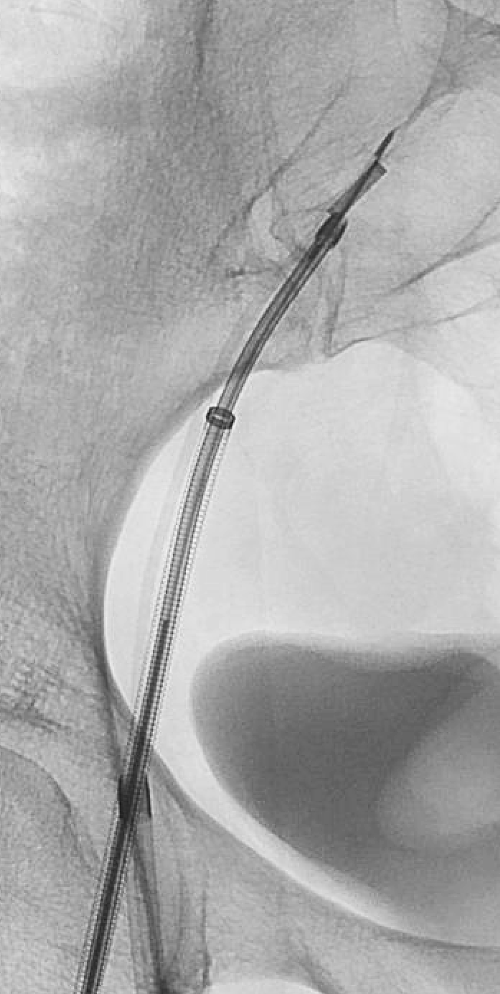

The initial venogram was performed from right common femoral access and a second high right great saphenous vein access is obtained. Through the second access, an intracardiac echocardiography (ICE) catheter is introduced and used to image the mass as shown in Figure 3; the mass can be visualized, along with color doppler identification of the adjacent right external iliac artery.

We then introduce a transjugular liver biopsy needle through the right common femoral vein access and perform endovascular biopsy using concomitant fluoroscopic and ICE guidance (Figures 4a and b). We have pathology on-site to perform adequate assessment of the specimens. The patient is diagnosed with a venous leiomyosarcoma and is referred for operative resection.